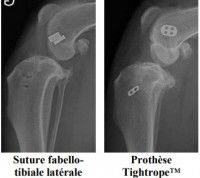

Il existe à ce jour deux types d’opération : la suture et l'ostéotomie.

Les techniques basées sur la suture sont plus adaptées pour les petits chiens et les chiens légers. Elles sont principalement réalisées de manière extra-articulaire (hors de l’articulation), la technique intra-articulaire (dans l’articulation) ayant donné des résultats inconstants.

Elles sont au nombre de deux :

Les techniques fondées sur une ostéotomie (coupe osseuse) modifient la biomécanique de l’articulation du genou en changeant l’action des muscles sur le haut du tibia. Elles présentent de meilleurs résultats chez les grands chiens, et permettent de réduire la progression de l’arthrite, qui n’en reste pas moins inévitable.

Là encore, elles sont au nombre de deux :